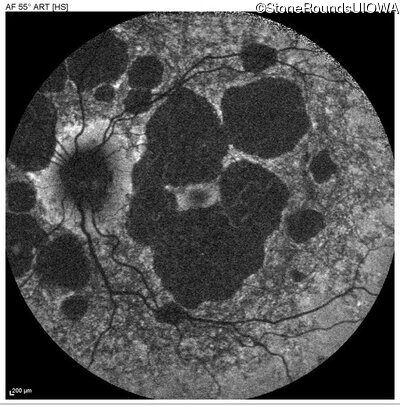

Blue Autofluorescence - Right - 20/30 +1

Exemplar

Blue Autofluorescence - Left - 20/30 +1